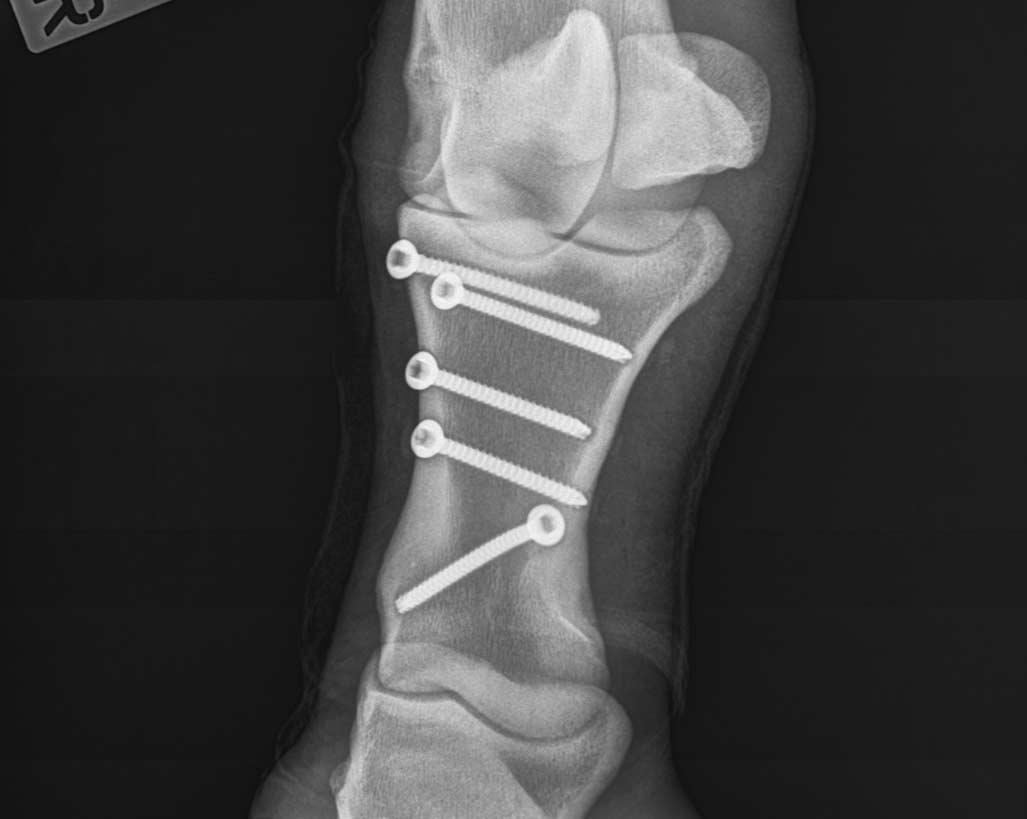

σε την εγχείρηση, ο οποίος ανέφερε: «Η επέμβαση διήρκησε πέραν της μιας ώρας και τοποθετήθηκαν 5 βίδες στο επίμαχο σημείο. Σε αυτό το σημείο θα ήθελα να επισημάνω ότι ο αριθμός των βιδών που τοποθετούνται καθορίζεται αναλόγως του μεγέθους του κατάγματος.

»Οι πέντε βίδες θεωρούνται φυσιολογικός αριθμός και έχει συμβεί και σε άλλες περιπτώσεις.

»Όσο για τη Ναύπακτο, μετά την επέμβαση μεταφέρθηκε στο ιπποφορβείο του Αλέξη Χαραλαμπίδη και μετά από δικές μου οδηγίες, παρέμεινε κλεισμένη στον στάβλο για τρεις περίπου μήνες, έτσι ώστε να επουλωθεί το κάταγμα.

Η ακτινογραφία με τις πέντε βίδες